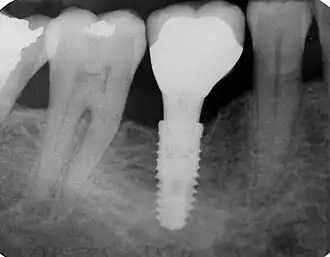

Implant dentaire

Implant dentaire en position 46